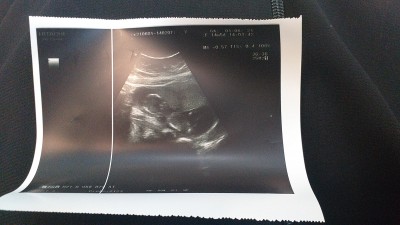

Kizlar tahmin yapabalicek varmi cinsiyet tahmini

Kizlar tahmin edebeliecek yazsin

Erkek gibi sanki doktor bişi demedimi

Demedi canim

uzak biraz ama erkek geçti içimden :)

Hadi bakalım hayırlısı tahmin bike yapmadı dr